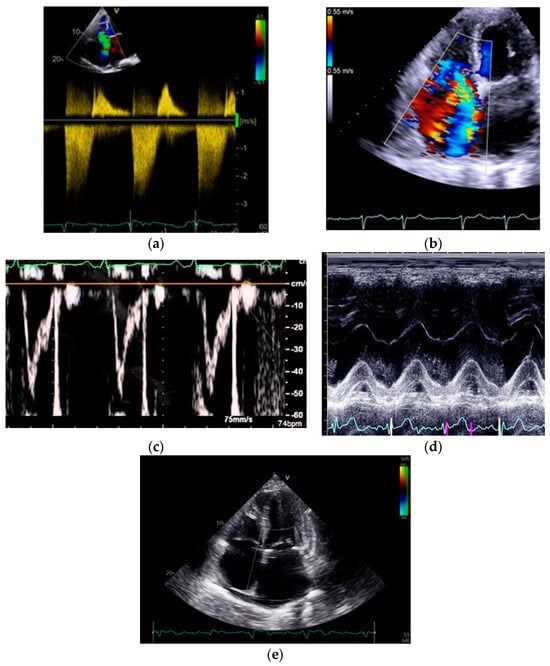

3.2. Tricuspid Regurgitation Velocity Peak (TRVpeak) and PASP Calculation

3.3. Right Ventricular Outflow Track Acceleration Time (RVOT-AT)

3.4. Pulmonary Regurgitation

3.5. The Potential Roles of the Echocardiography in the Differential Diagnosis of Pulmonary Hypertension

4.1. Tricuspid Annular Plane Systolic Excursion (TAPSE)

4.2. Right Ventricular Size

4.3. Right Ventricular Function

4.4. Right Atrium Size and Function

4.5. Pericardial Effusion